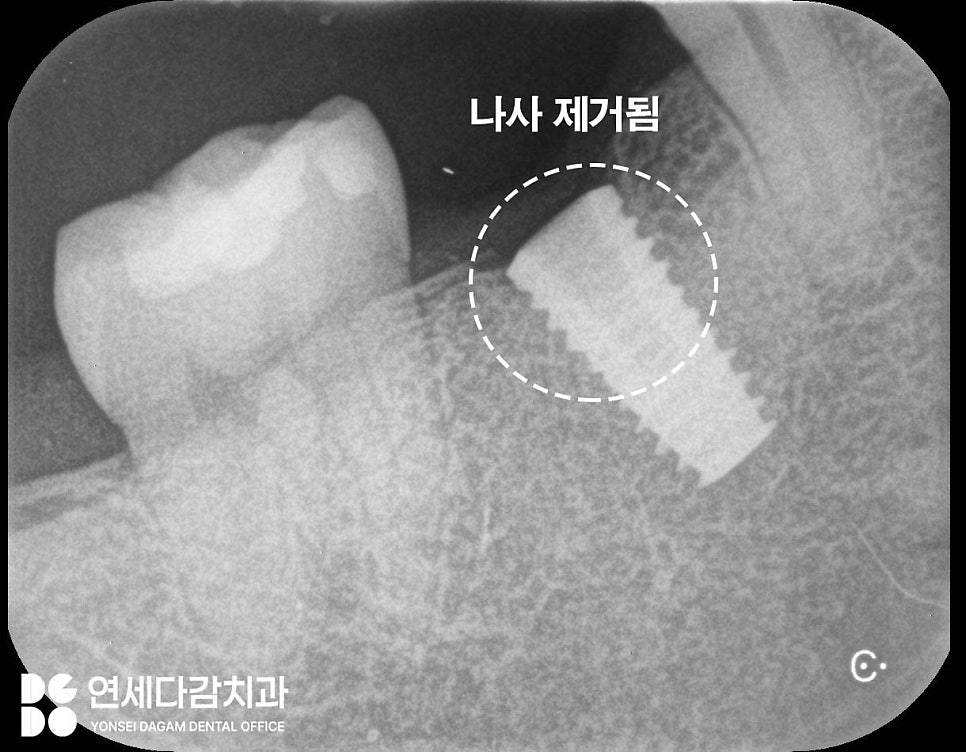

거여역 치과 에서 보여드린 증례는

다행히도 두 번째 방법을 이용하여

얇은 잇몸 치료 전용 팁을

장착하여 진동을 줬을 때

잘 빠진 모습입니다.

내부 모습도 나사 일부가

잘 빠져나온 것을 확인한 뒤

이후 새로운 보철물을 제작하여

기능을 회복할 수 있습니다.

이렇게 적절한 방법으로

접근한다면 재수술 없이도

해결할 수 있는 경우가 있습니다.